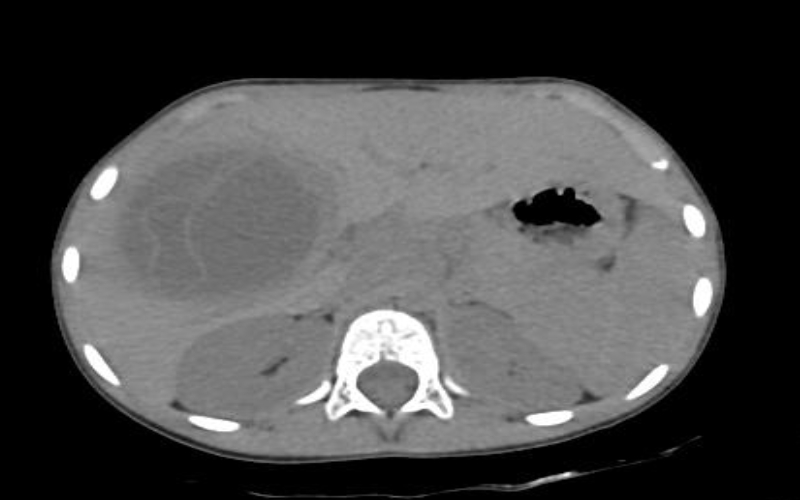

হাইডাটিড সিস্টের লক্ষণ হলো- জ্বর, কাশি, বুকের মাঝখানে চাপ, হাঁটলেই শ্বাসকষ্ট অনুভূত হওয়া। প্রাথমিকভাবে “সিজনাল ফ্লু” মনে হতে পারে। বুকের এক্স-রে করলে পানির ঢেউয়ের মতো অস্বাভাবিক ফ্লুইড লেভেল দেখা যাবে। তবে এটা মোটেও সাধারণ নিউমোথোরাক্স না। সিটি স্ক্যান করার মাধ্যমে “হাইডাটিড সিস্ট” স্পষ্ট বোঝা যাবে।

হাইডাটিড সিস্ট ফেটে গেলে ভেতরের অংশগুলো পানির ওপর ভাসমান ওয়াটারলিলি সাইনের মত দেখায়, যেন মনে হবে বুকের ভেতরে পদ্মফুল ভেসে আছে। এটাই মূলত ফেটে যাওয়া এন্ডোসিস্ট -এর ফোল্ডেড মেমব্রেনস, যার মধ্যে ভেসে আছে ডটার সিস্টস। কখনো এটা সাপের মতো ভাঁজ হয়ে সার্পেন্টাইন সাইনও তৈরি করে।